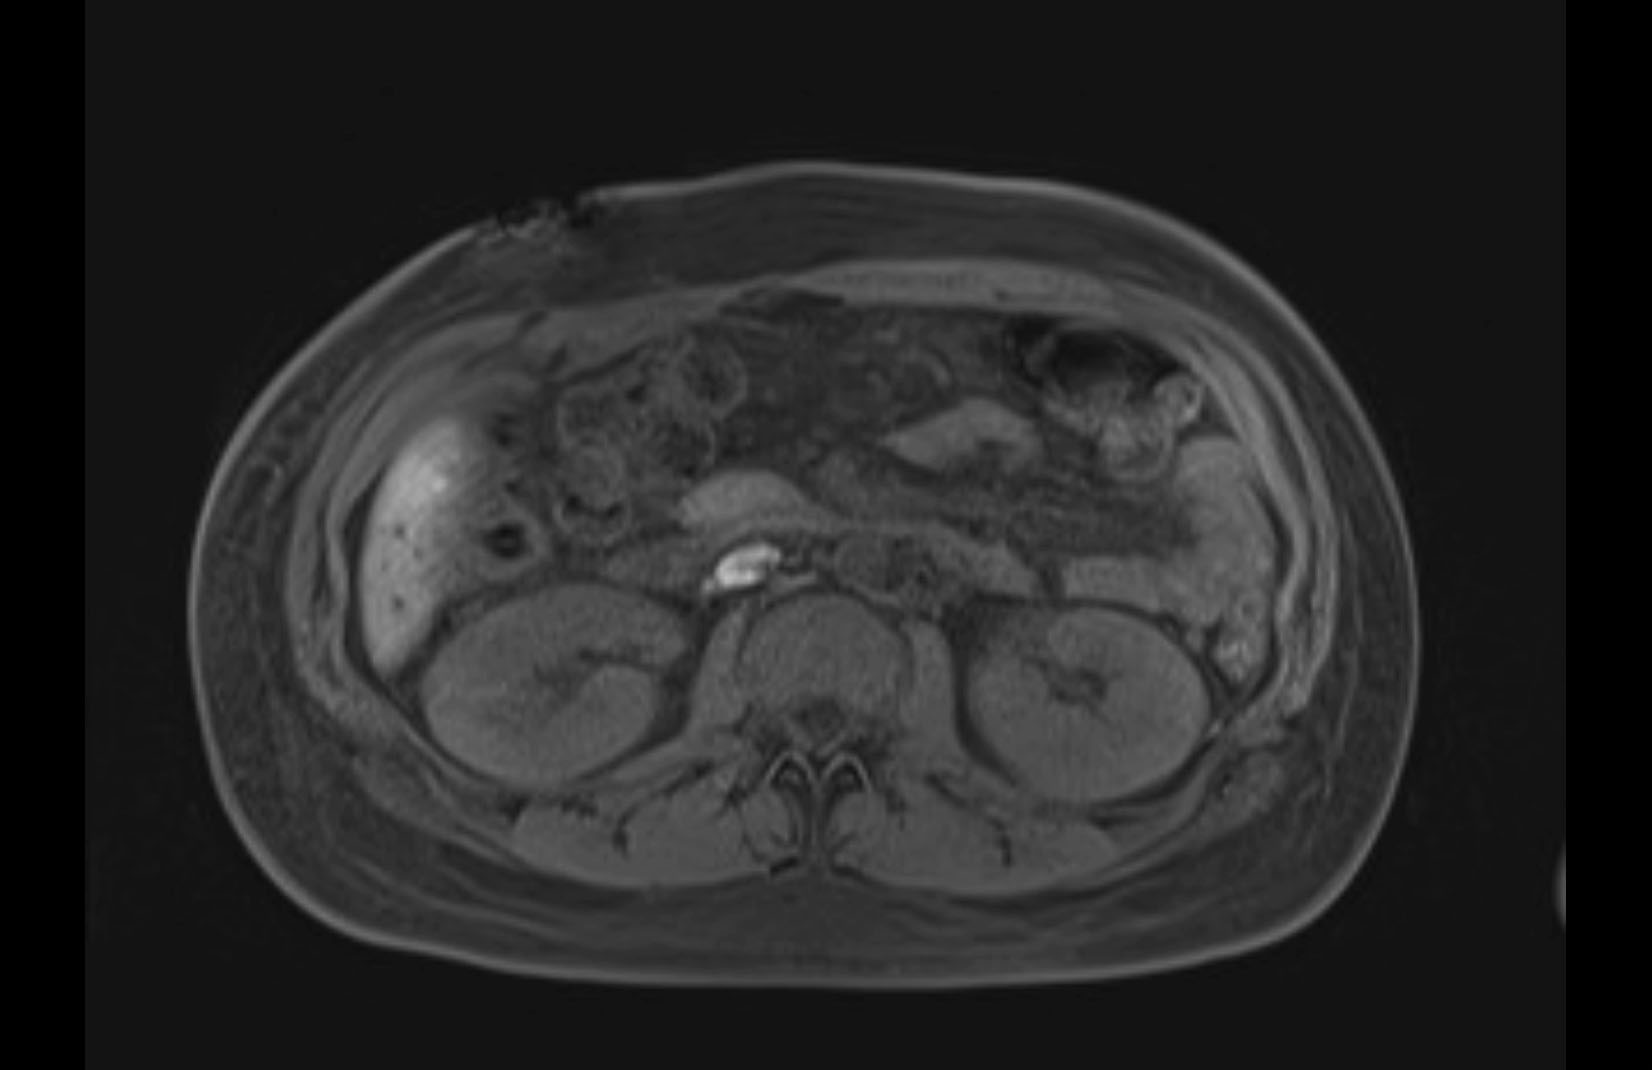

Imaging Analysis

Look through the patient's CT scan to identify any areas of concern for the necessary procedure.

MRI T1

Based on initial findings, which issue(s) would you be most concerned about?